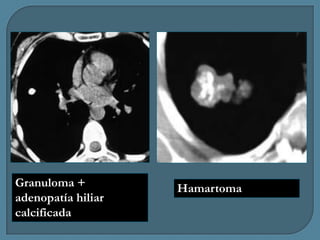

Granuloma +

adenopatía hiliar

calcificada

Hamartoma